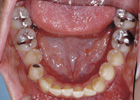

歯を抜いて治療した例 その1

治療途中

治療後